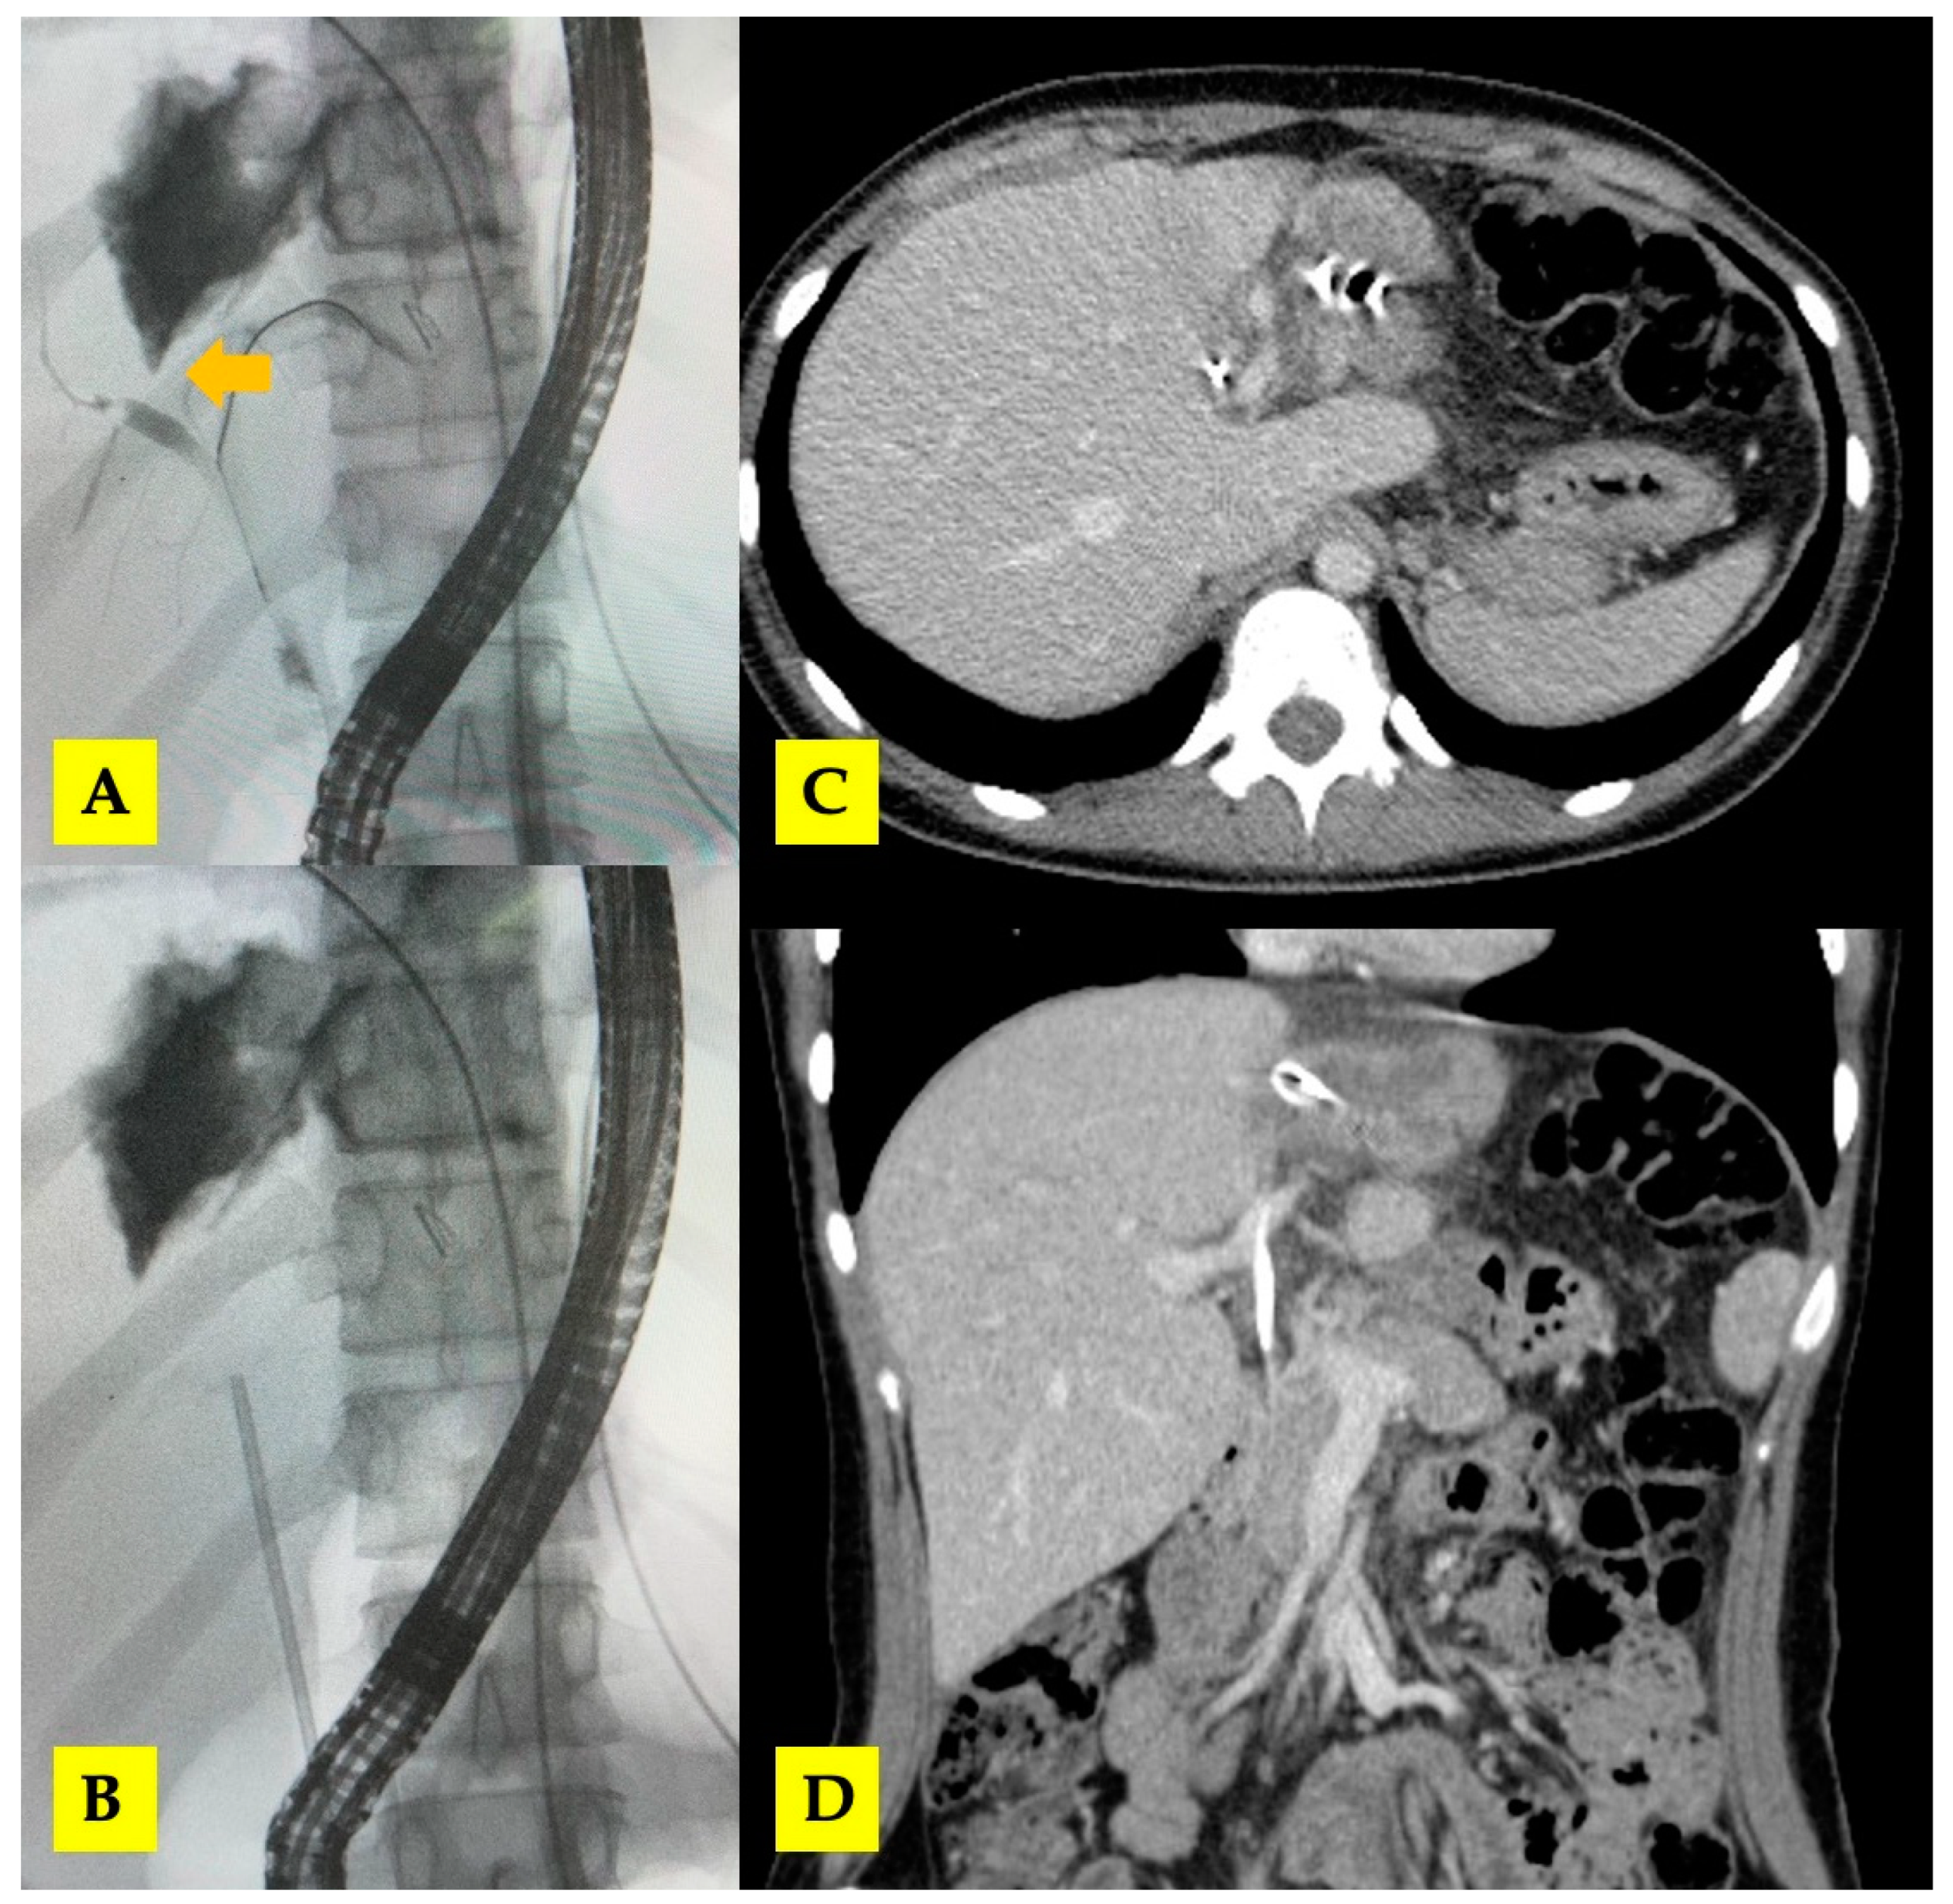

3.2. Case 2